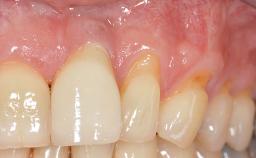

Early Implant Placement, Contour Augmentation, and Autologous Connective-Tissue Graft Using a Tunneling Technique to Replace an Upper Incisor with Generalized Gingival Recession

Variations in soft-tissue volume, evidenced either by an overabundance (Evian and coworkers 1993; Levine and McGuire1997; Dolt and Robbins 1997) or by a deficiency of soft or hard tissue can complicate implant-supported rehabilitations in the esthetic zone (Lorenzana 2008; Lorenzana and coworkers 2009). The present case illustrates the replacement of a failing upper left lateral incisor complicated by generalized severe gingival recession in the esthetic zone.

Soft Tissue Anatomy Intact Defective

Soft Tissue Contour and Volume Significantly deficient